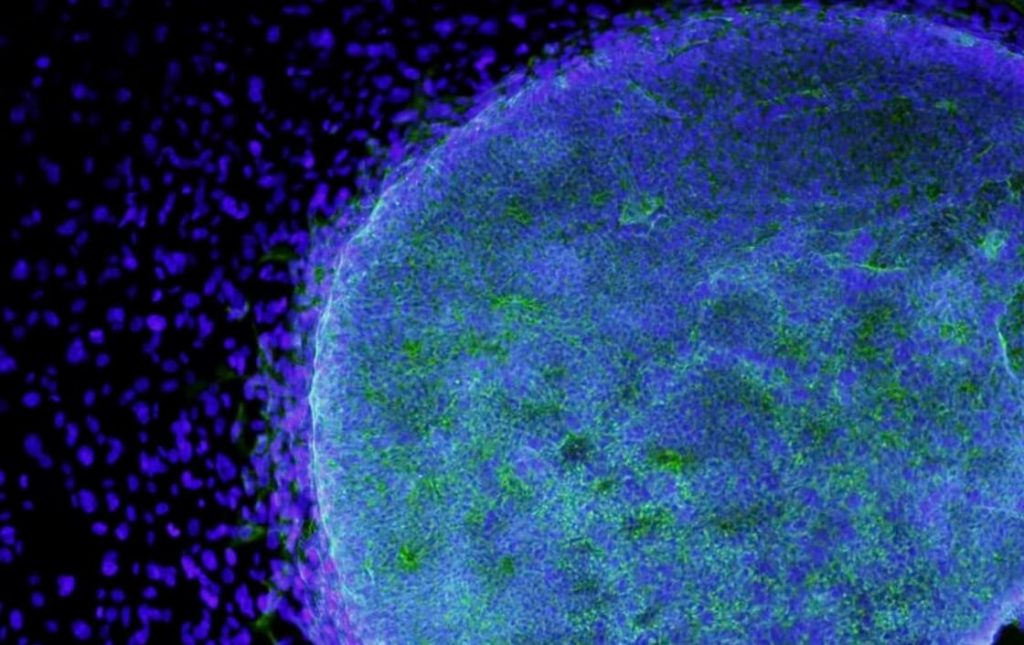

Los fenómenos íntimos de la división celular pueden reducirse a dos modelos: la división directa o amitosis y la indirecta o mitosis.

La división directa o amitosis es la menos frecuente, teniendo una importancia secundaria, pues queda reducida a células muy especializadas.

Consiste en que el núcleo sin modificar sensiblemente su estructura se alarga, se estrecha en el centro y por fin se parte en dos.

En algunos casos el citoplasma sigue la misma suerte, formándose dos células hijas; en otros no se segmenta quedando así constituida una célula con dos o más núcleos formando un plasmodio.

Este tipo de reproducción directa se lleva a cabo mediante un proceso llamado mitosis. Durante la mitosis, el núcleo de la célula se divide en dos núcleos idénticos y luego la célula se divide en dos células hijas idénticas, cada una con un núcleo idéntico y el mismo conjunto de cromosomas.